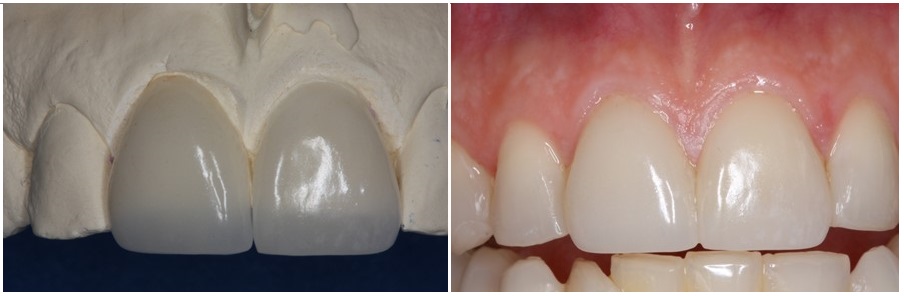

Στην φωτογραφία που ακολουθεί βλέπουμε τις αποκαταστάσεις τοποθετημένες στο εκμαγείο και συγκολλημένες στο στόμα.

καθώς και το αποτέλεσμα που προσφέρουν στα δόντια μετά την συγκόλληση τους σε αυτά.

Ακολούθησε η κατασκευή των όψεων στους δύο κεντρικούς τομείς, τις οποίες βλέπουμε στην φωτογραφία που ακολουθεί τοποθετημένες στο εκμαγείο και συγκολλημένες στο στόμα.